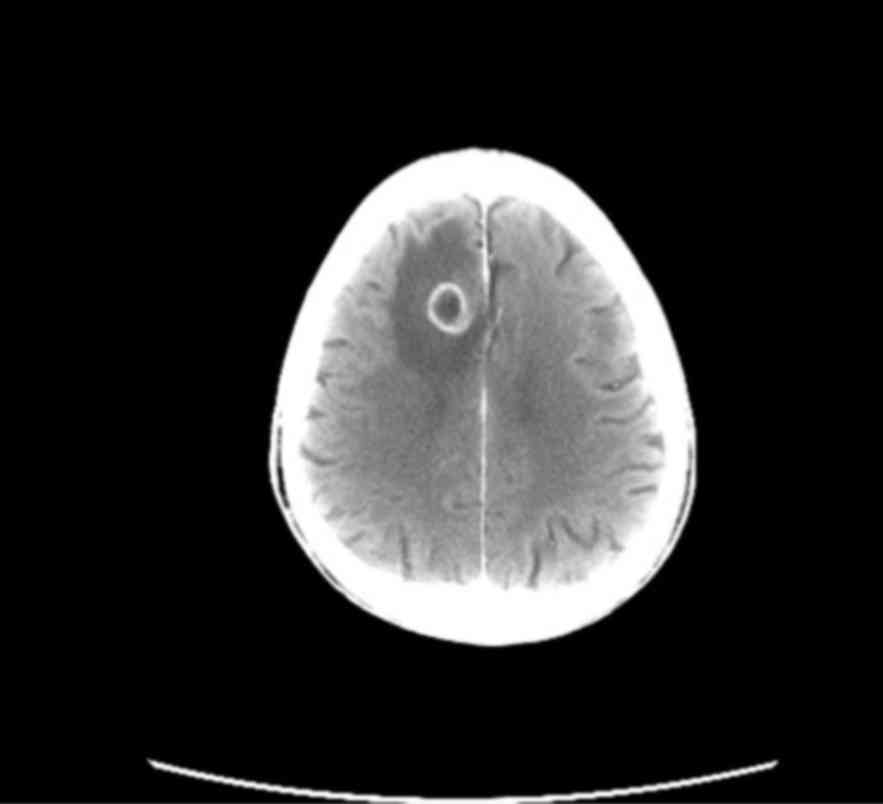

Long-term survival in a patient with metastatic squamous cell lung carcinoma: A case report

Non-small-cell lung cancer (NSCLC) is the most common malignancy in industrialized countries, with a 5-year survival rate of only ~15%, as the majority of the patients have advanced-stage disease at diagnosis and the treatment options are limited. Squamous cell carcinoma the second most frequent type of NSCLC and is closely associated with cigarette smoking. We herein present the case of a 72-year-old male smoker, diagnosed with stage IV squamous cell lung carcinoma, with a solitary brain metastasis. After the diagnosis, stereotactic radiotherapy was performed on the brain metastasis. Following radiotherapy, chemotherapy with carboplatin + paclitaxel was initiated. However, after 2 cycles of chemotherapy, disease progression in the lung was observed. Therefore, second-line treatment with pemetrexed was started, which was discontinued after 2 cycles due to further disease progression. Third-line treatment with erlotinib was then administered, with notable benefit, as the patient remains alive after 6 years of treatment with a good performance status. The mutation status of EGFR was unknown.

Figure 1

Figure 2

Figure 3

Figure 4